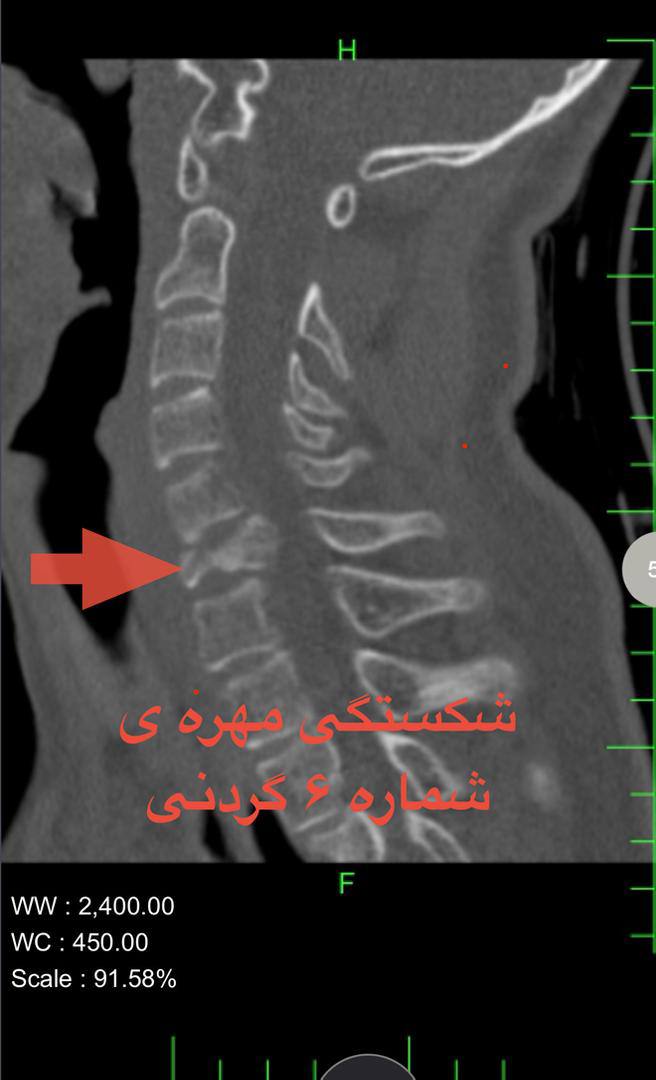

این عمل پیشرفته که اولین مورد در منطقه جنوب سیستان و بلوچستان است، با همکاری تیمی ششنفره متشکل از جراحان مغز و اعصاب، متخصصان بیهوشی و پرستاران، طی شش ساعت بر روی یک جوان ۱۸ ساله که به دلیل حادثه تصادف دچار شکستگی، جابجایی مهره گردن و فشار بر نخاع شده بود انجام شد.